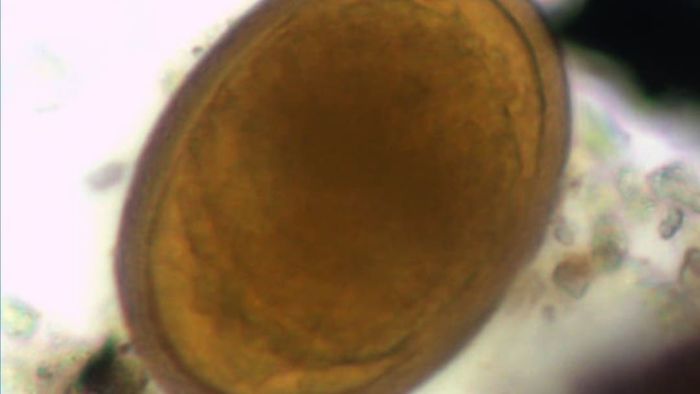

From this data, the researchers concluded that the Helmins strongyle mentioned by Hippocrates was likely what modern medicine refers to as roundworm. They further speculated that the Ascaris worm described by Hippocrates likely referred to two different parasites, which are known today as pinworm (not found in this study) and whipworm (shown below).

A whipworm egg | ElsevierAlthough historians had previously speculated that Hippocrates's patients on Kea suffered from roundworm, the discovery of Ascaris is a surprising twist. Earlier research, relying only on Hippocrates's writings rather than physical evidence, suggested that what he described as Ascaris was likely pinworm, and another worm he referenced, Helmins plateia, was probably a tapeworm. However, the latest study found no traces of either of these parasites. Instead of pinworm eggs, the researchers discovered whipworm, another small, round parasite. (The researchers note that pinworms may have existed in ancient Greece, but their delicate eggs may not have survived.) This soil analysis has already shifted our understanding of the intestinal health issues faced by the ancient Greeks on Kea.